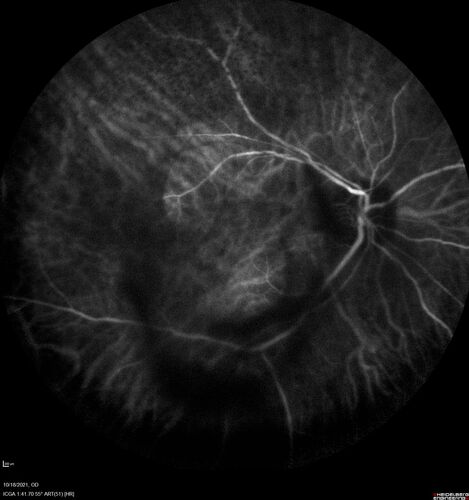

Severe Syphilitic Placoid Chorioretinitis

68 year old man 3 months ago the vision started fading in both eyes.  Just sitting here he can see some light out of his right eye. The patient denies any recent illness or travel.

VA: OD: LP, OS: 4/200

IOP: 9, 13

Anterior segment: 1+ cell/ 2+ flare OU and 2+ NS and anterior vitreous cells

Labs Reactive RPR 1:256, FTA-ABS - reactive - Patient was admitted to hospital for IV PCN and recovered vision almost completely in the left eye and some in the right eye.